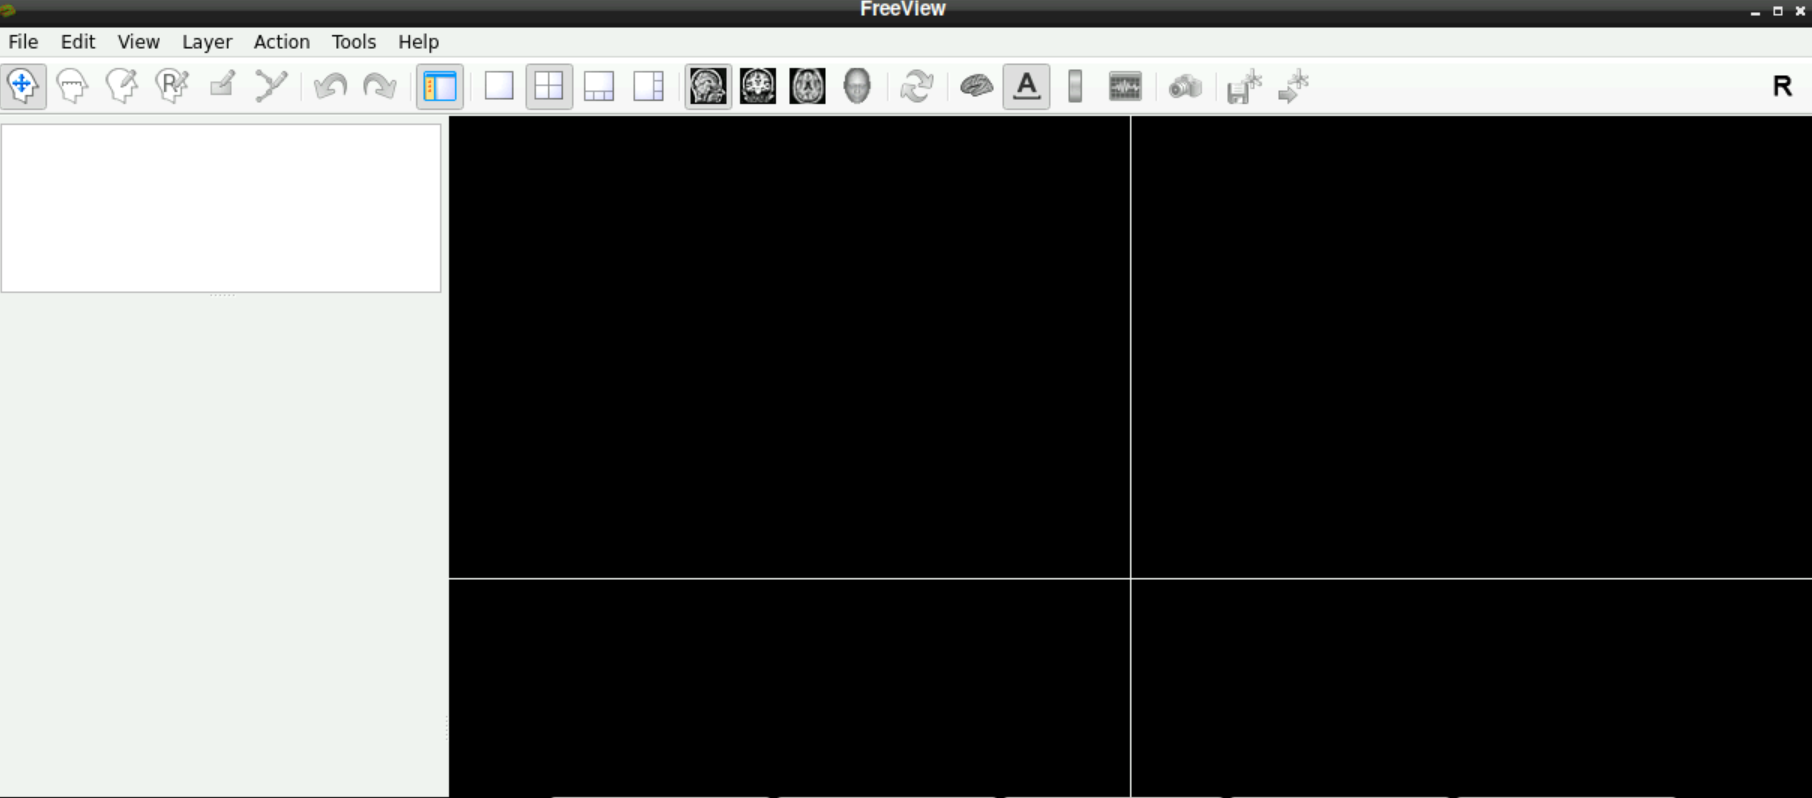

\(\to\) When freeview opened successfully, it should look like this:

1.2 Load a functional volume